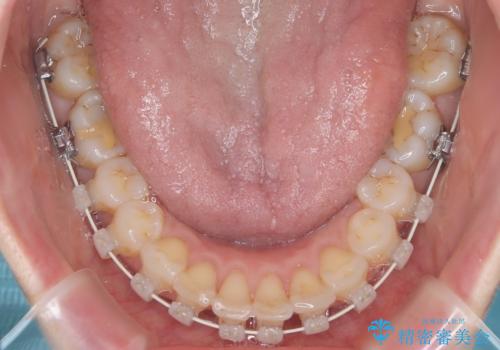

治療では、白いブラケットとホワイトワイヤーを使用し、矯正装置が目立ちにくいよう配慮しました。歯列を拡大しながら適切に歯を移動させ、IPRを併用することで、無理なくスペースを確保しました。見た目に配慮しながら、歯の凸凹をスムーズに整え、噛み合わせも改善。患者様からは「装置が思ったより目立たず、歯並びがきれいになって嬉しい」との声をいただきました。